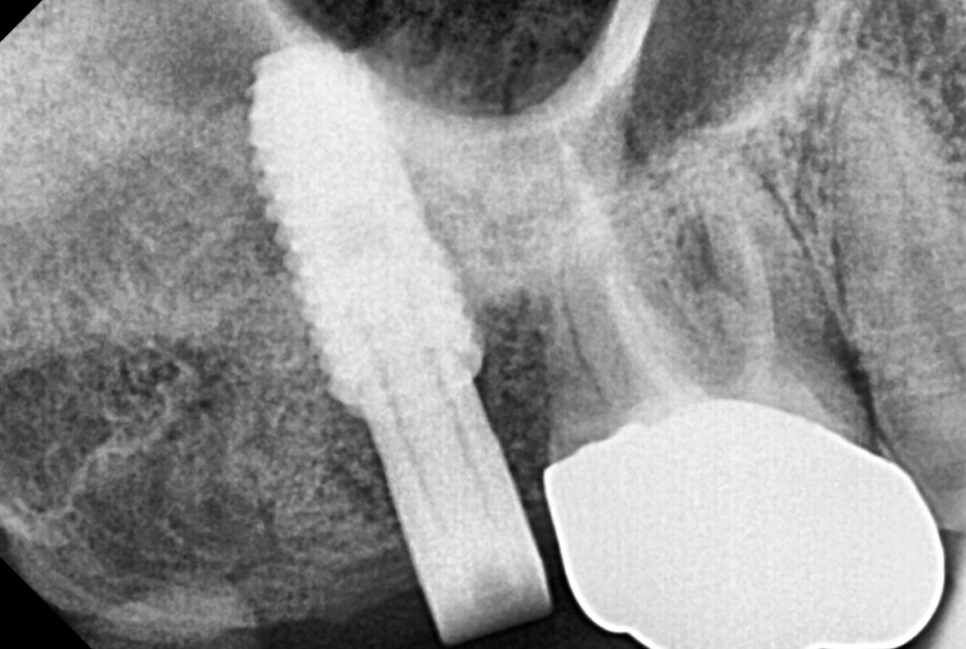

24.06.07

4개월 정도 충분히 기다려준 후

기둥을 만들어 주었습니다.

24.06.27

강동구 임플란트 보철까지 완성된 사진입니다.

보철 크기가 옆에 금니에 비하여

작게 느껴지실텐데요.